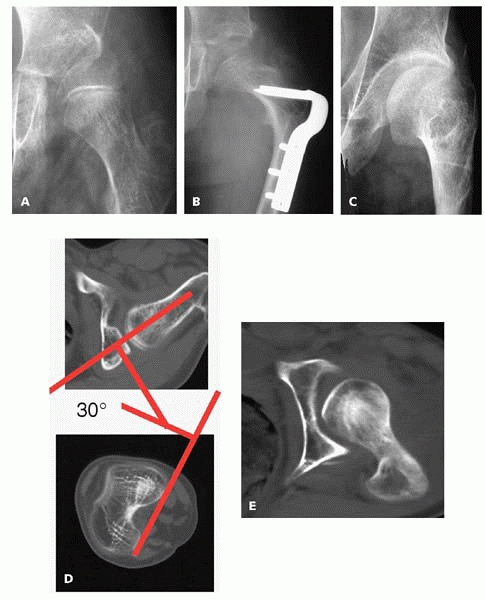

adducted hip from adducting further. Do not overdo the derotation! Most

out the back (Fig. 14-4). The posterior

acetabulum is an impossible place to increase the femoral head coverage

with an acetabular osteotomy, so don’t put the femoral head back there

where it can’t be protected. In children with low bone density, it is

safer to delay weight bearing or aggressive range of motion after the

hip reconstruction. The fixation can cut out easily (Fig. 14-5).

![]() |

|

▪ FIGURE 14-4 Too much “DR” in a “VDRO?” Partial hip subluxation (A) was treated with a VDRO (B) and Dega pelvic osteotomy. (C)

Five years after healing and hardware removal, this AP radiograph shows a rotational abnormality that is difficult to interpret, and the hip has a severe fixed internal rotation contracture. (D) A CT scan shows 30 degrees of anteversion. Since this was felt to reflect primarily soft-tissue contracture, he had a lengthening for the adductor, gluteus minimus and medius, fascia lata, and anterior hip capsule. If there would have been any femoral retroversion, this would have had to be combined with a femoral derotation. (E) This followup CT scan obtained one year after the releases demonstrates a much improved relationship of the femoral head to the acetabulum. On examination, external rotation has been restored. (Courtesy of F. Miller, MD.) |